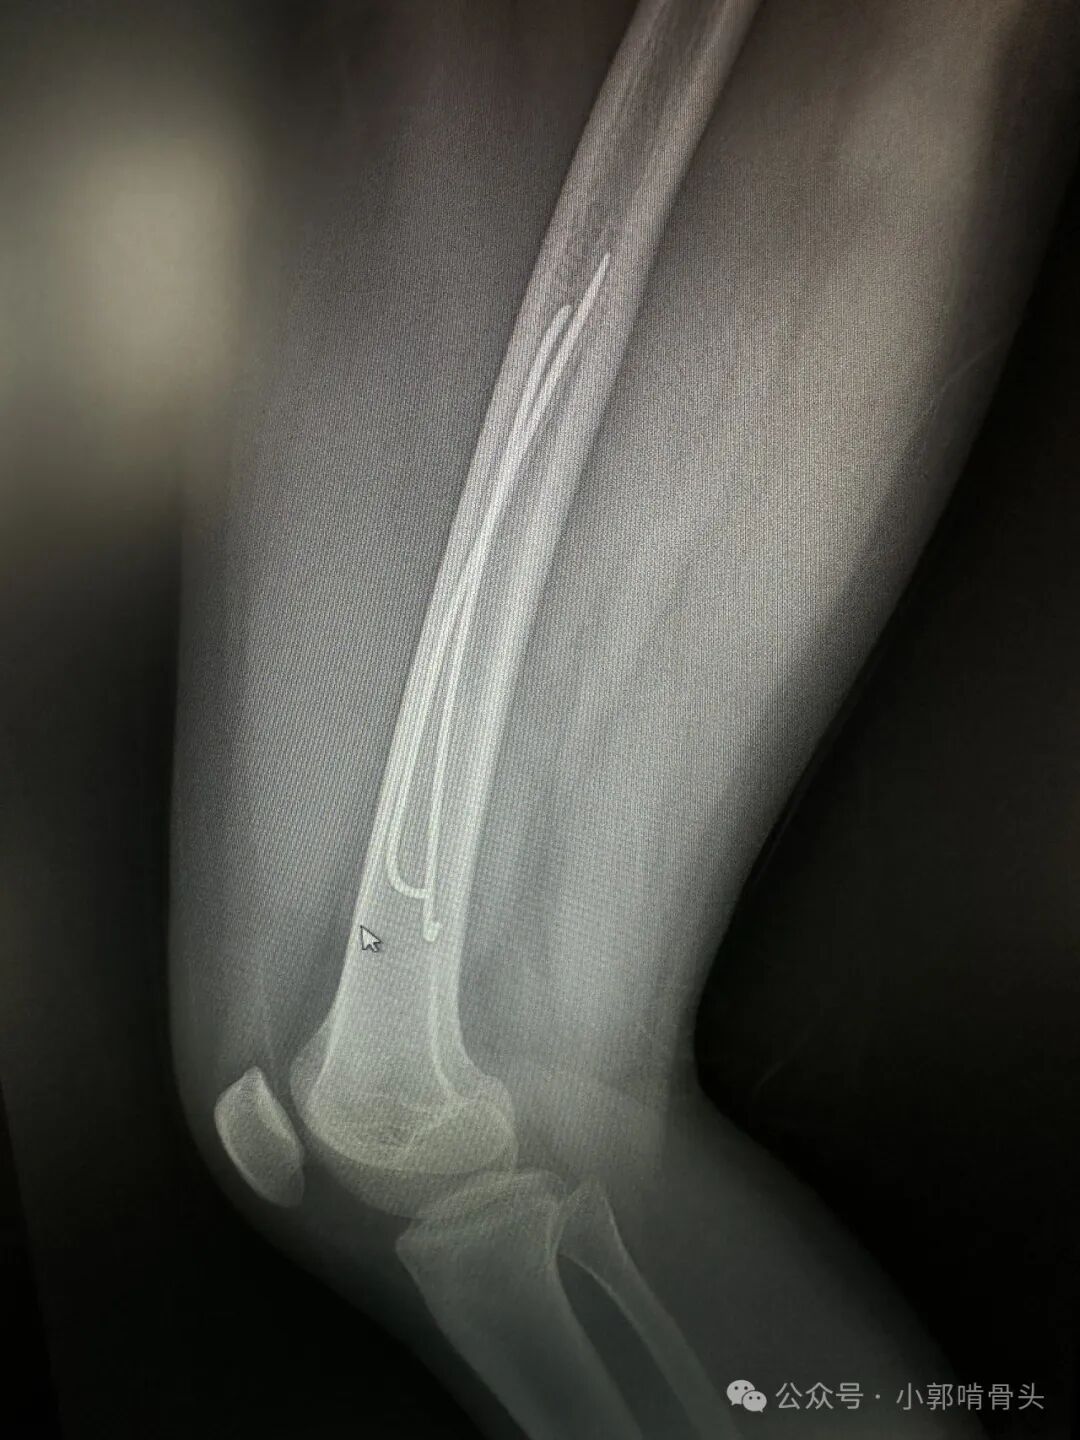

3岁因股骨干骨折行弹性髓内钉治疗,15年一直未取,现局部钉尾处不适要求取出。推测股骨长长的潜力是否近端优于远端。